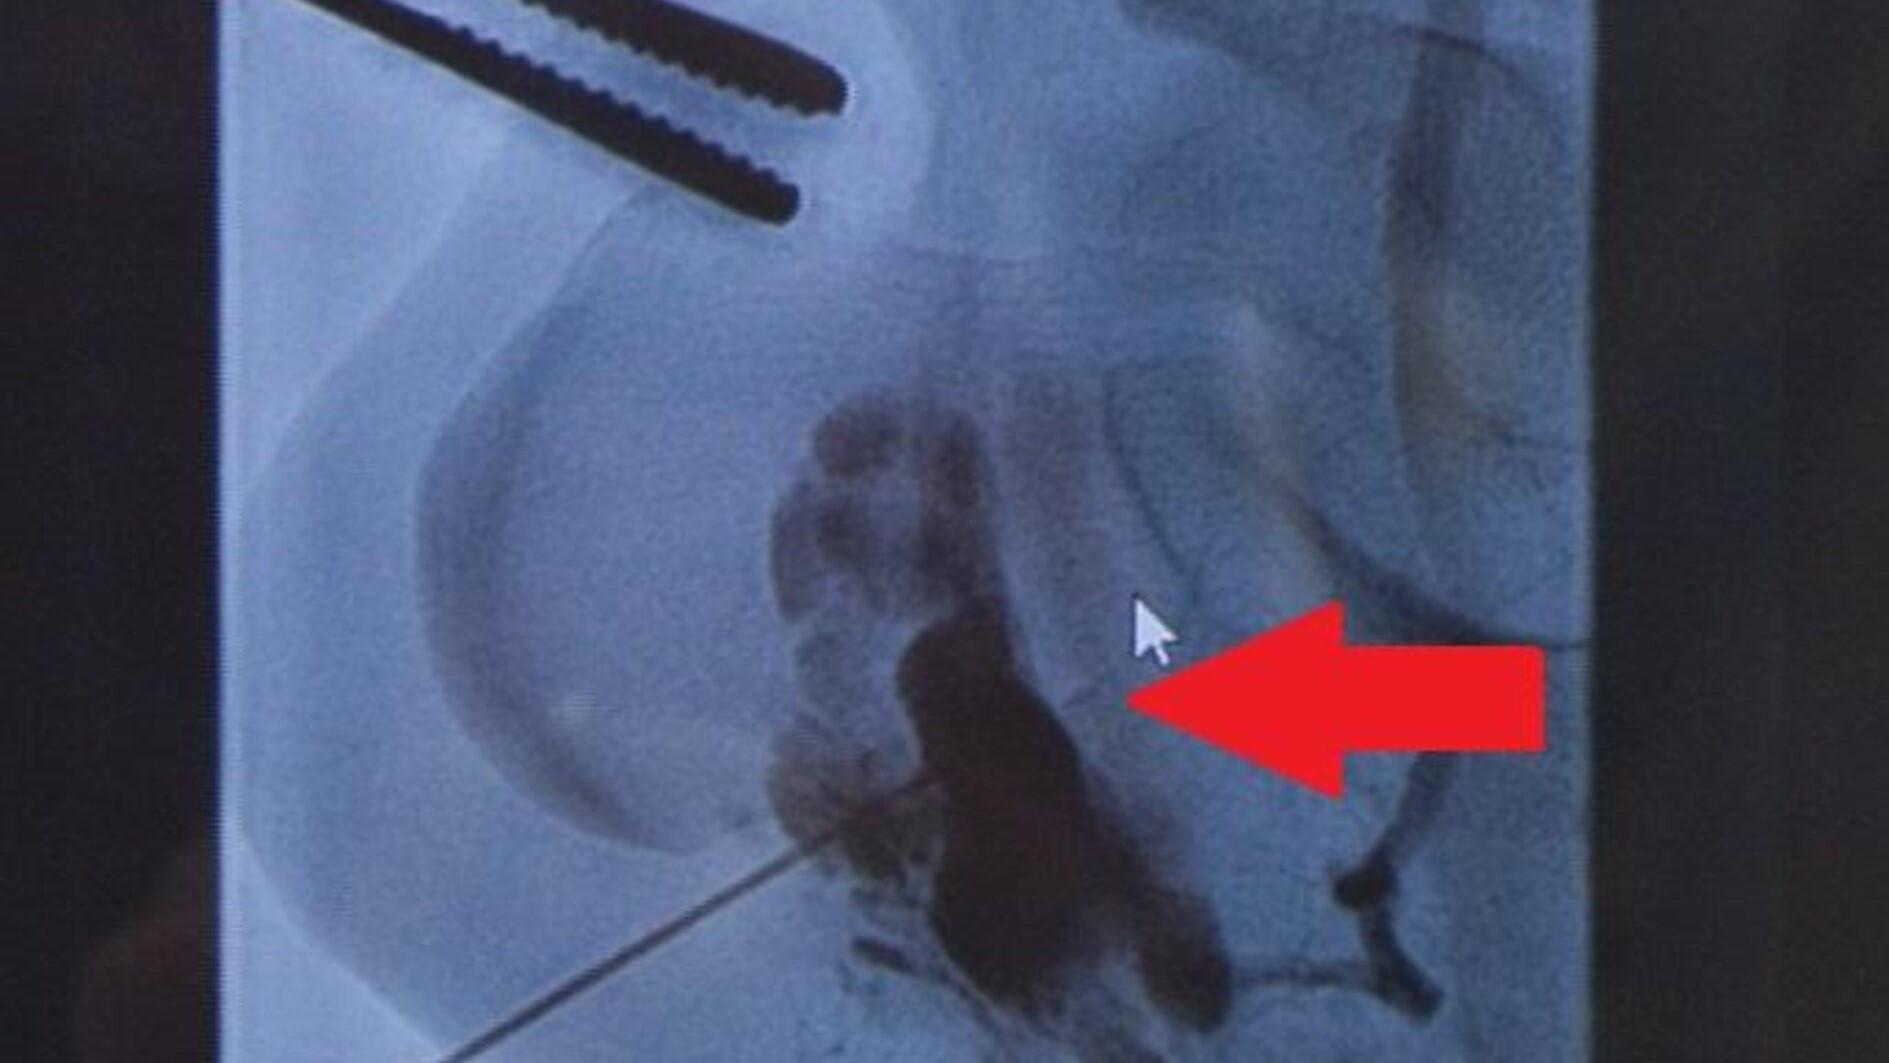

Merve Ay, 23, who lives in the southeastern province of Diyarbakır, struggled for 12 years with a vascular tumor that was detected in the heel of her left foot when she was only 8 years old.

"It is very rare for this tumor to be in located in the foot, it is almost non-existent. It was in a position where it was constantly pressing on that vascular formation; there was a danger of bursting because it was constantly under pressure," he said.